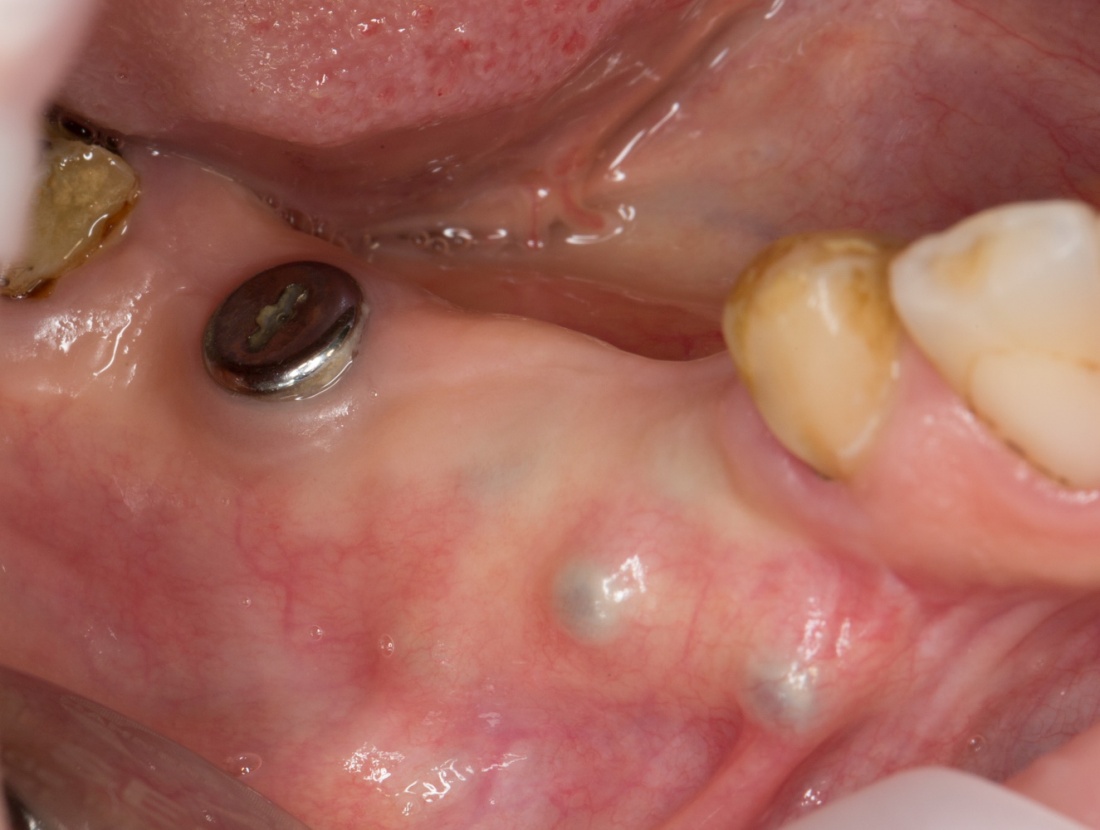

Остеопластика или «наращивание костной ткани» при имплантации — выбор метода и отдаленные результаты.